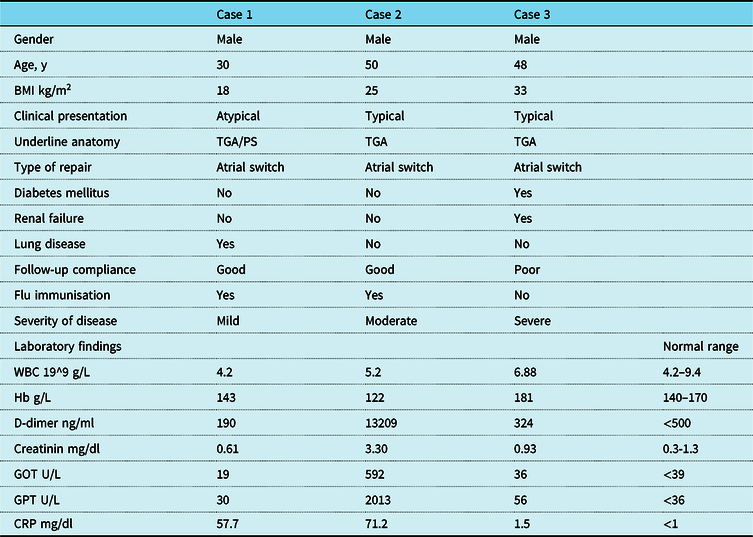

Continuous positive airway pressure was started. Arterial gas-analysis with continuous positive airway pressure (FiO2 60% PEEP 10) showed a PO2 oxygen/FiO2 of 200. Table 1 summarises lab results.

Table 1. Summary of clinical characteristics and laboratory findings

BMI = body mass index; CRP = C-reactive protein; GOT = glutamic oxaloacetic transaminase; GPT = glutamic-pyruvic transaminase; TGA = transposition of great arteries; Hb = haemoglobin; WBC = white blood cells

However, the epidemiology and clinical course of COVID-19 in patients with CHD is still undefined. The patients here reported, despite a similar anatomy and physiology, had very different clinical course (Table 1).